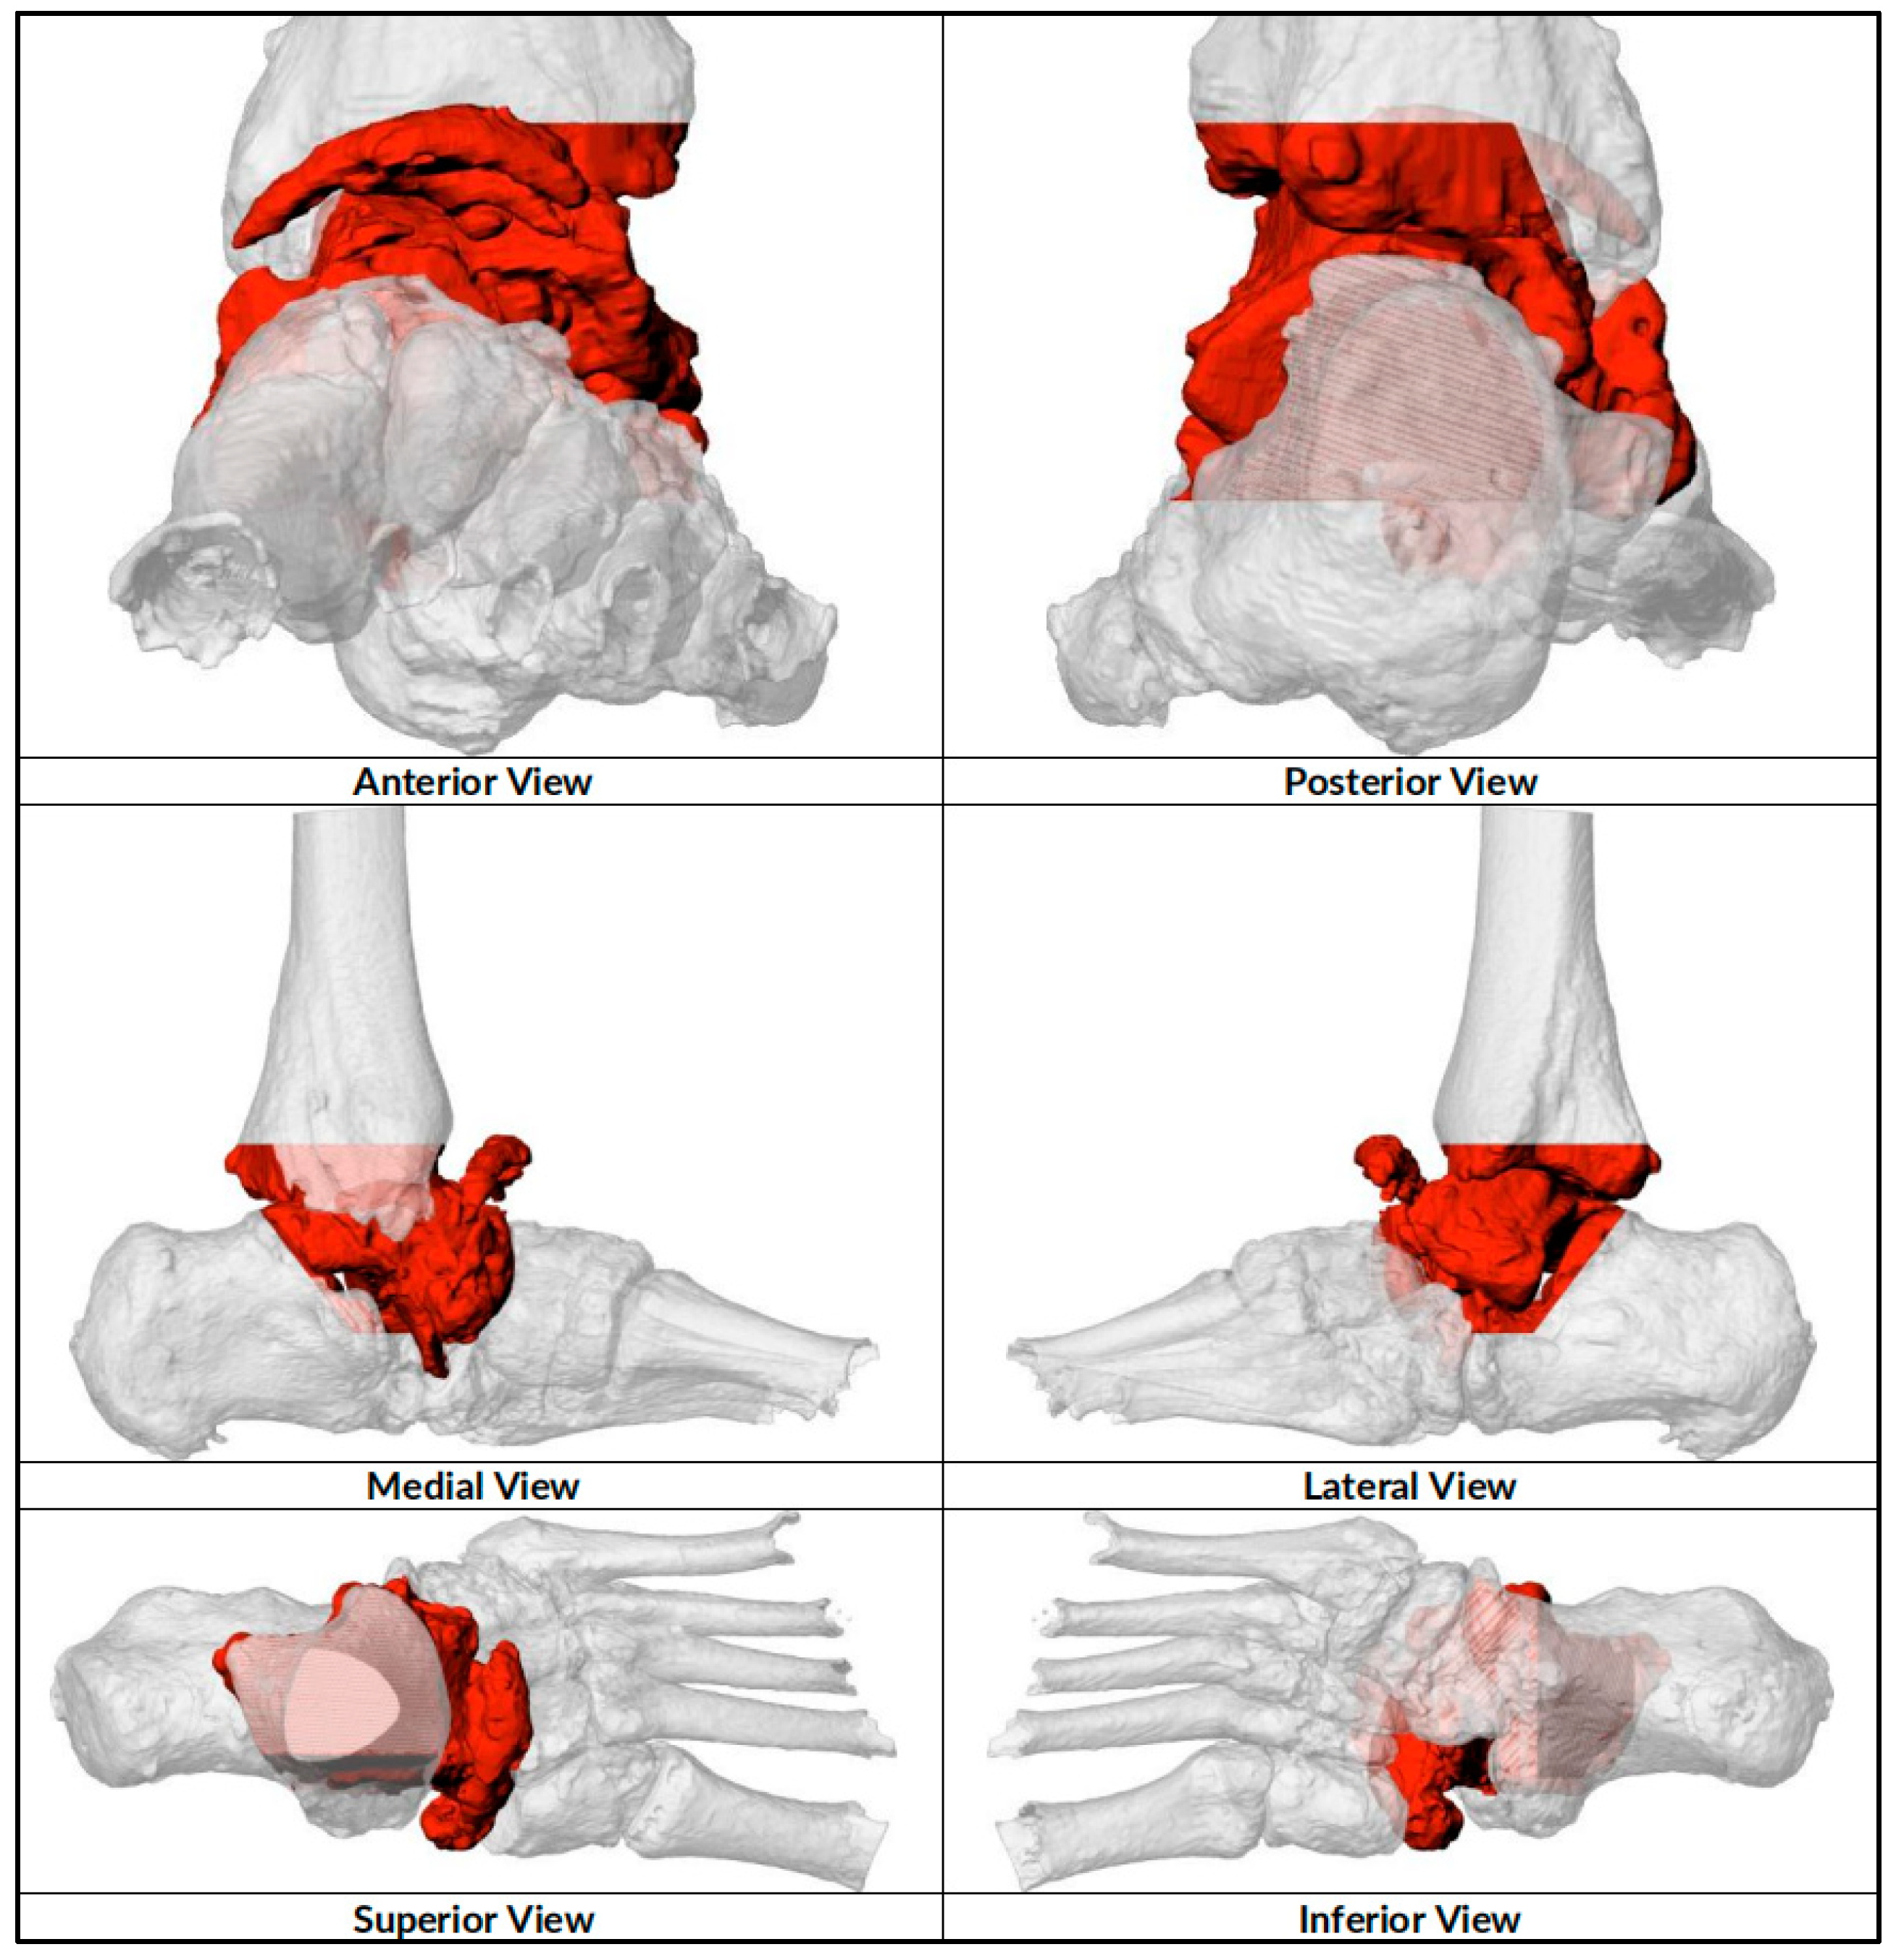

2.1. Preoperative Planning

2.2. Surgical Technique